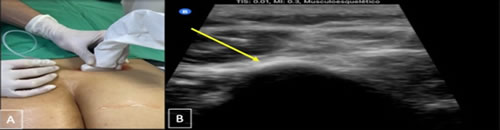

Se realizó un estudio de tipo observacional, retrospectivo, en pacientes diagnosticados con dolor lumbar crónico, signos y síntomas de atrapamiento de nervios cluneales o clunealgía llevados a bloqueo. Se revisaron las historias clínicas obteniendo información demográfica y clínica. Los criterios de inclusión son pacientes mayores de 18 años de edad con antecedente de patología lumbar por imágenes de resonancia o radiografía, con uno o más síntomas, dolor lumbar, irradiación a glúteo o miembro inferior, disestesia, exacerbación del dolor con cambios en la postura lumbar, y/o signos de clunealgía evidenciados en el examen físico de la historia clínica, a quienes se les realizó bloqueo analgésico de nervios cluneales (Figura 1 A y B) en el Hospital Universitario San José y Clínica Los Nogales en Bogotá durante el 1 de septiembre de 2019 al 31 de abril de 2021. Se excluyeron pacientes a quienes se les realizó otro tipo de procedimiento analgésico tipo bloqueos de bandas miofasciales y bloqueos facetarios con mejoría del dolor.

Fig. 1. A. Técnica de abordaje guiado por ultrasonido en los dos hospitales. Paciente en decúbito prono, transductor de alta frecuencia sobre el plano transversal de espina ilíaca posterior, la fascia toracolumbar y el borde lateral del músculo erector de la columna, al final del glúteo mayor se observa el glúteo medio conocido este punto como túnel graso. B: se realiza infiltración de medial a lateral al nivel de la espina ilíaca posterosuperior y sobre fascia toracolumbar, en el nervio cluneal superior (flecha amarilla) con solución analgésica con lidocaína al 1 % sin epinefrina 100 mg o bupivacaína al 0,25 % + betametasona 6 mg (volumen total 5 mililitros) a nivel perineural e interfascial. Observando la fascia toracolumbar y el músculo erector de espina separarse.